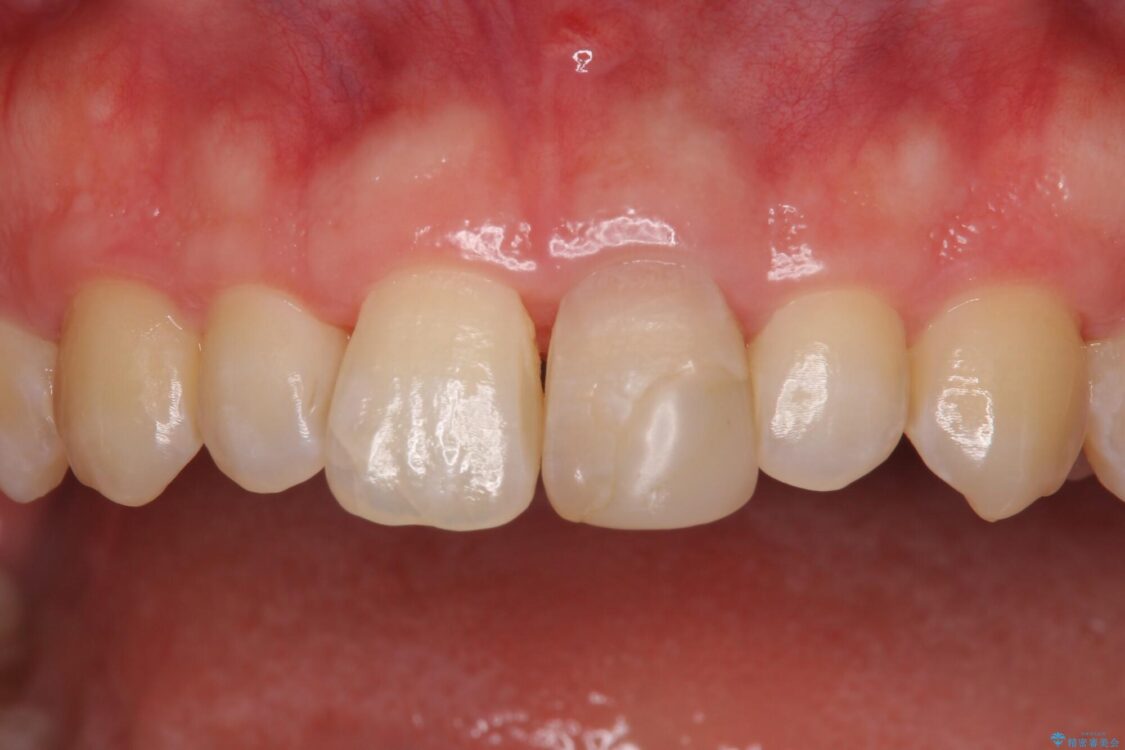

治療後

• 変色した前歯をオールセラミッククラウンに 治療後画像

神経を取り除いた歯は時間とともに変色してきます。

クリーニングやホワイトニングでは改善できないため、オールセラミッククラウンなどによる補綴治療が必要となります。